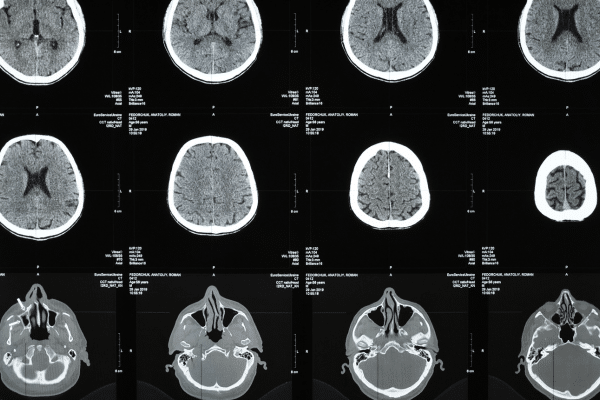

CT scans have become one of the most reliable tools in modern medicine. Their ability to quickly diagnose internal problems has saved lives, guided surgeries, and provided peace of mind for millions. But as these scans become more routine, a serious warning is gaining attention. New research suggests that up to 5% of all annual cancer diagnoses in the US may be tied to the very scans meant to protect health. This silent risk, driven by overuse and excess radiation exposure, raises urgent questions about how these technologies should be used.

CT scans have reshaped how doctors identify and treat illness. They offer a detailed view of the body, from bones and blood vessels to organs and muscles, making them essential for detecting everything from internal bleeding to tumors. Because of this, CT scans are used frequently and across all age groups.

The power of a CT scan comes from its use of X-rays, which create cross-sectional images of the body that can be assembled into a 3D view. Unlike MRIs, which use radio waves and magnets, CT scans rely on ionizing radiation. This is the same type of high-energy radiation used in cancer treatments and is known to damage DNA at the cellular level.